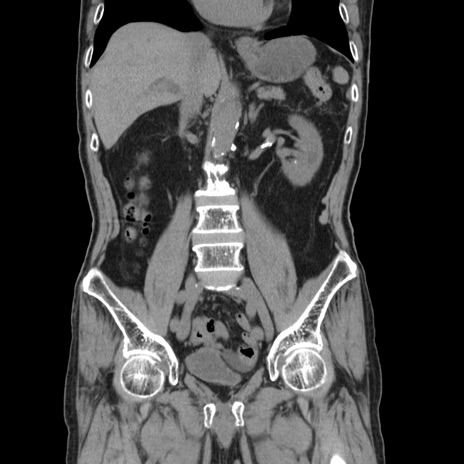

矢状断像